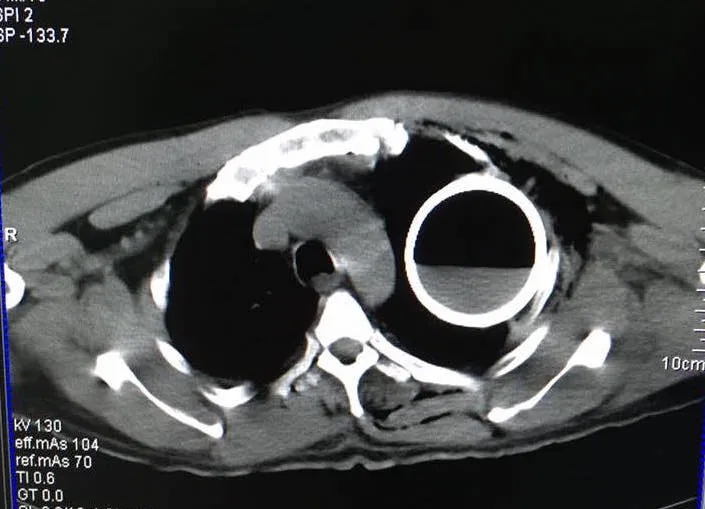

Chụp CT scaner, các bác sĩ phát hiện vỏ chai nước khoáng trong lồng ngực bệnh nhân

Các bác sĩ chỉ định chụp X Quang cho ông B. và phát hiện trong vùng ngực có một vỏ chai. Sau đó, các bác sĩ cho CT scaner để đánh giá cụ thể tổn thương thì xác định vỏ chai nước khoáng Thạch Bích nằm trong lồng ngực. Ông B. còn bị gãy 2 xương sườn nhưng không có tổn thương nghiêm trọng khác.